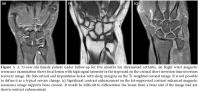

All the cases had a radiograph which was either normal or with suspicious erosions. Magnetic resonance imaging showed 73 (81.1%) bone erosions over different sites in carpal bones, four (4.4%) in distal radius, four (4.4%) in distal ulna, and nine (10%) in proximal metacarpal heads. All the erosions were single or multiple and non-adjacent focal while showing low signal intensity on T1-weighted images with contrast enhancement and high intensity signals on T2-weighted images (Figure 1-3). No bone marrow edema signs which are seen in the advanced stages of the disease as diffuse or converging signal changes were observed. Capitate was the site having the highest number of erosions with 20 (27.3%), followedby triquetral, scaphoid, lunate, trapezoid, hamate, trapezium, and pisiform having 18 (24.6%), 11 (15%), eight (10.9%), six (8.2%), six (8.2%), three (4.1%), and one (1.3%) erosion, respectively.

On MRIs, erosions appear as trabecular bone loss with sharp margins accompanied by cortical defect. Erosions can be more clearly observed following intravenous gadolinium injection.

Bone erosions

Presence of bone erosions were evaluated in 15 different anatomical regions (8 carpal bones, distal radius, distal ulna, 5 metacarpal heads). All the erosions were defined as single or multiple focal areas with sharp and regular margins causing defects in the cortical and subcortical bone marrows. Lesions with low signal intensity on T1-weighted images, high signal intensity on T2-weighted images and enhanced after contrast material administration were identified as bone erosions.